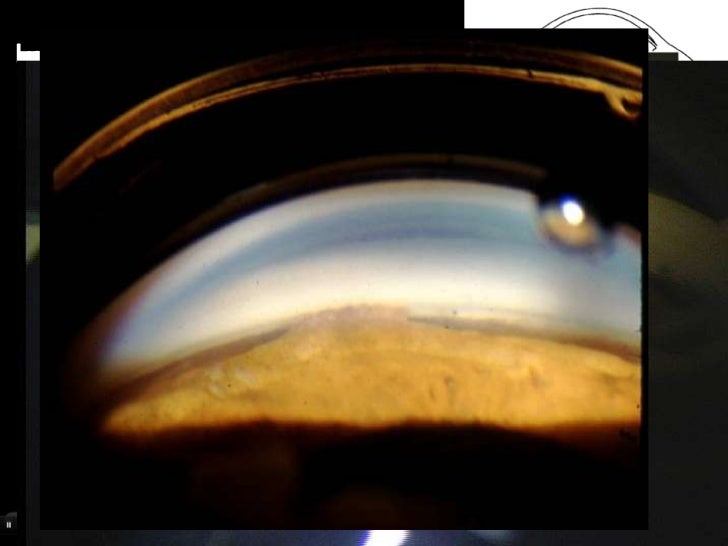

Gonioscopy Recording . The eye should be examined carefully with the slit lamp before beginning gonioscopy. 1 that's a pretty poor track record. the key indications for performing gonioscopy are: the key to correctly interpreting and recording your view is to always perform the procedure in the same. today, gonioscopy is a critical exam technique used for visualizing the anterior chamber angle. gonioscopy is a clinical procedure used to inspect the anatomical structures of the anterior chamber angle (the angle). Why is this the case? gonioscopy is the process of assessing the anterior chamber in order to diagnose abnormalities of the intraocular. In many instances, i suspect doctors haven't learned to do it well.